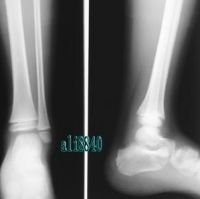

(1)分清伤势的轻重:如果脚扭伤后能持重站立,勉强走路,说明扭伤为轻度,可自己处置;如果脚扭伤后足踝活动时有剧痛,不能持重站立或挪步,按着疼的地方在骨头上,并逐院摄片诊治,可能有骨折,骨折的话是不能自己处理的,必须接受医生的正确处理。

注意是否骨折